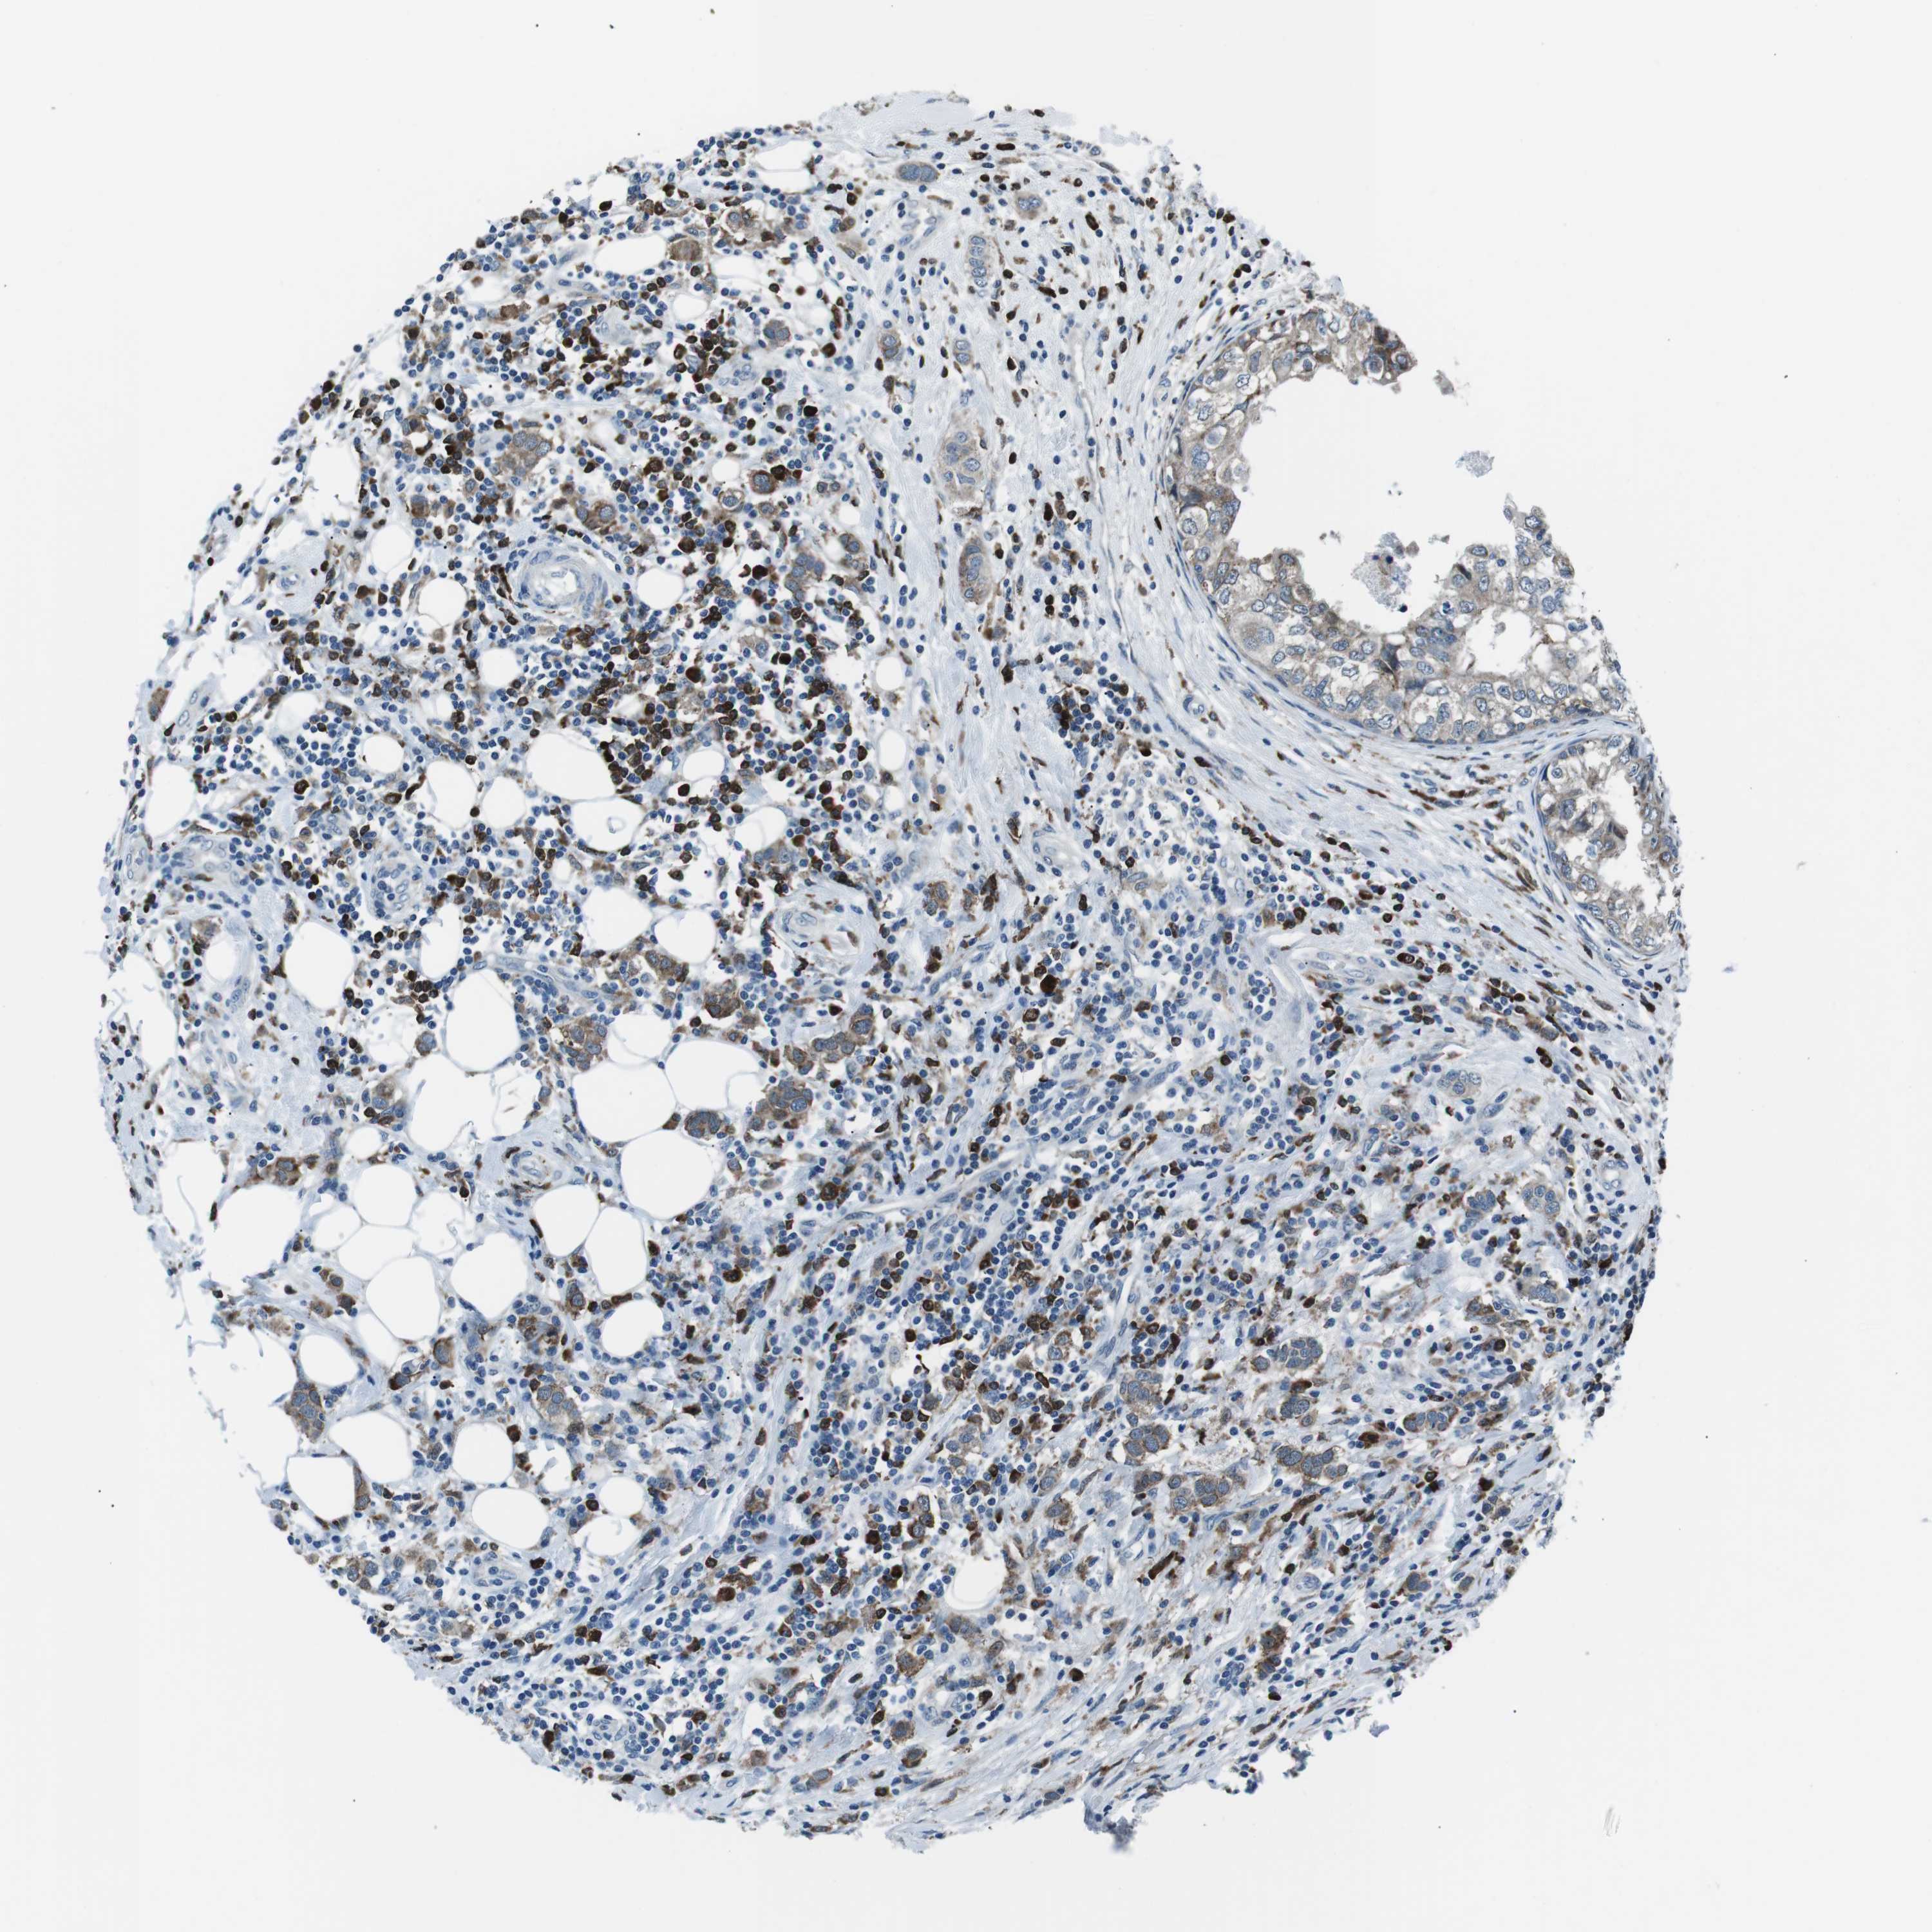

CANCER BREAST CANCER Show tissue menu

BRCA TCGA BRCA VALIDATION PROTEIN EXPRESSION